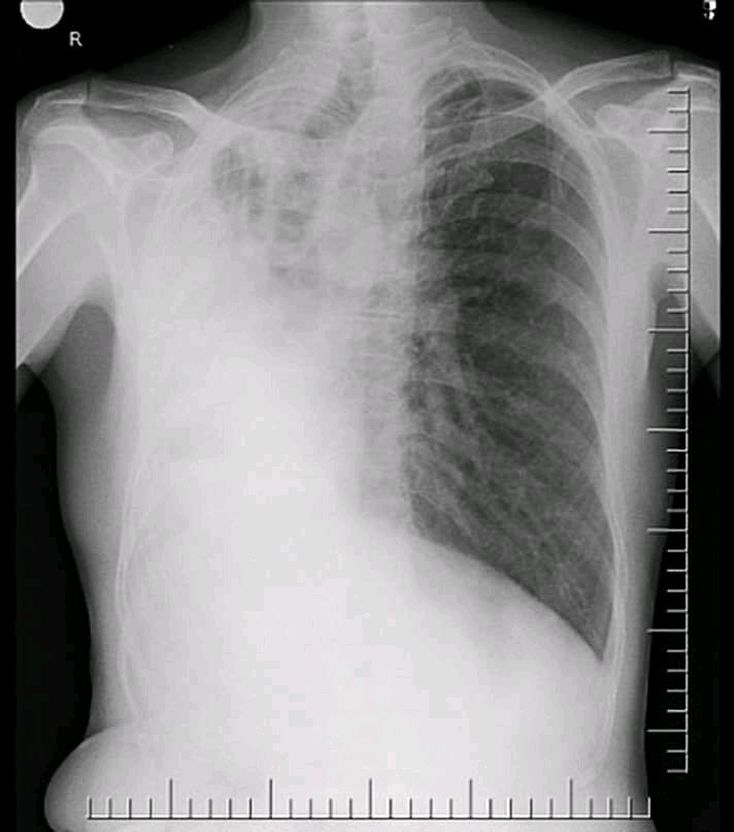

What is your diagnosis?

Pneumonia, pneumonectomy.

Massive rt sided pleural effusion with lung collapse